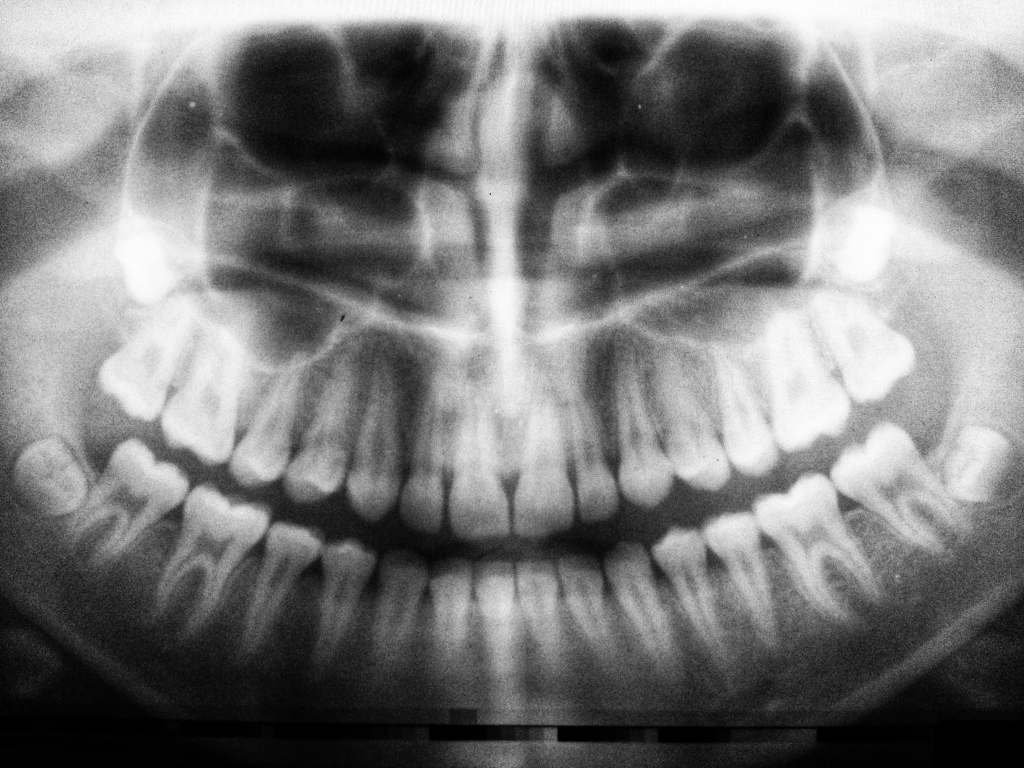

Medicines dedicated to improving a specific condition and resulting in side effects create concern. The FDA 2022 released a safety communication regarding severe dental health issues, like tooth loss, cavities, oral infections, and tooth decay, occurring in people who used Suboxone Sublingual Film, a buprenorphine medication. These patients have filed legal claims against Indivior, the drug manufacturer.

Suboxone Sublingual Film is a medicine that has been used to treat opiate addiction. In the past few months of 2023, the number of lawsuits for Suboxone dental decay has gone up. Almost all plaintiffs shared that they faced permanent tooth loss and dental damage that led to other expensive treatments and reduced their quality of life.

The medicine is often used as a film or tablet that dissolves inside the mouth a few times daily. In his lawsuit, King claims that Suboxone should have warned its users. It has an acidic pH of 3.4, which results in acute dental injuries.

It’s this change that has made more users experience dental side effects. The reports include the following:

• Tooth extractors

• Several dental decays

• Chipped or cracked teeth

• Tooth loss